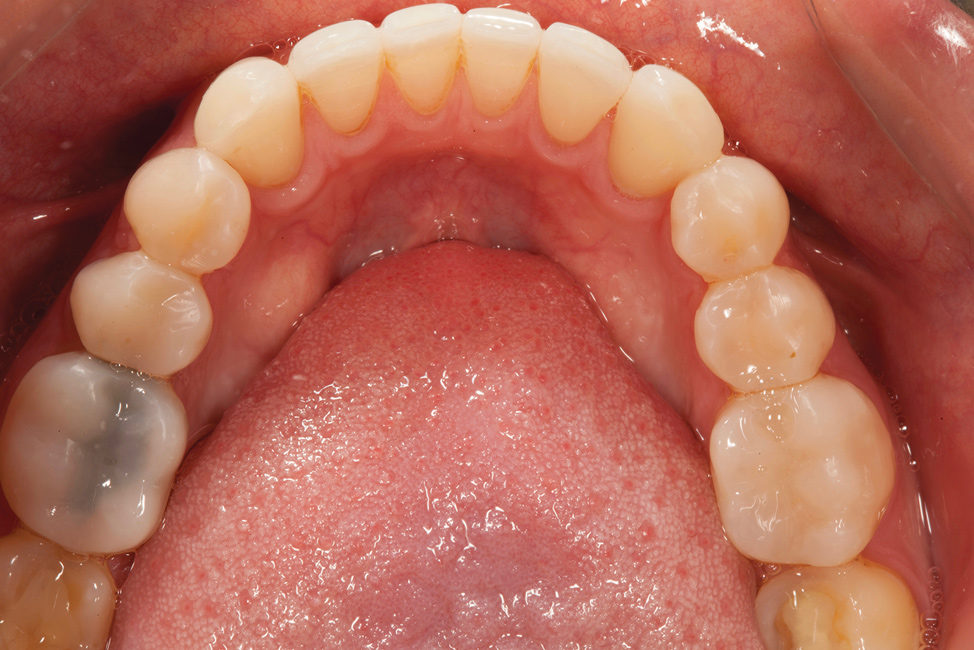

Fig 3. Preoperative occlusal view of lower arch with orthotic in place.

Figure 3

A comprehensive examination was carried out, and preoperative photographs were taken (Figure 1 through Figure 4). The patient presented with fair oral hygiene and slight, generalized tissue inflammation. Caries and defective restorations were detected on teeth Nos. 4, 5, 13, and 14. The crown on tooth No. 12 was showing signs of leakage, and although the endodontic access cavity had been temporarily restored with composite, this endodontic re-treatment was acceptable and the tooth was otherwise symptom-free. Erosion was present on most of the posterior teeth and the cuspids, and abrasion was noted on teeth Nos. 4, 5, 10, 11, 20, 21, 22, 28, and 29. An examination of the patient's muscles, joints, and bite revealed no joint sounds, a normal range of motion, and negative joint load and immobilization tests.

The patient's removable dental orthotic covered the lower bicuspids and first molars. With the orthotic in place, there was shim stock contact on all posterior teeth and on the second molars that were not covered by the appliance. However, there was no incisal overlap and a lack of anterior guidance.9When the orthotic was removed, no more than three teeth touched, and a 2-mm space between the posterior teeth made mastication difficult.

The dentofacial examination revealed a low smile line with no incisor display when the lips were in repose. The anterior teeth were chipped and worn, and their overall color was darkened. The buccal corridors were deficient, and the failing crown on tooth No. 12 was visible in a full smile.